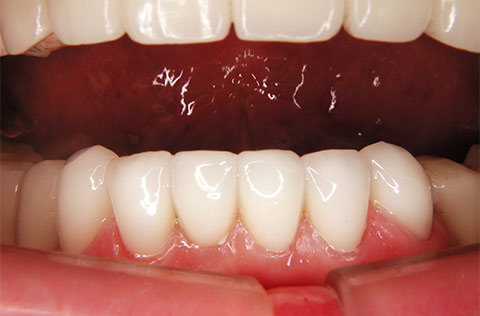

ジルコニアの被せ物で、削れてきた6本の前歯を整えたケース。神経を抜かずに治療できた。